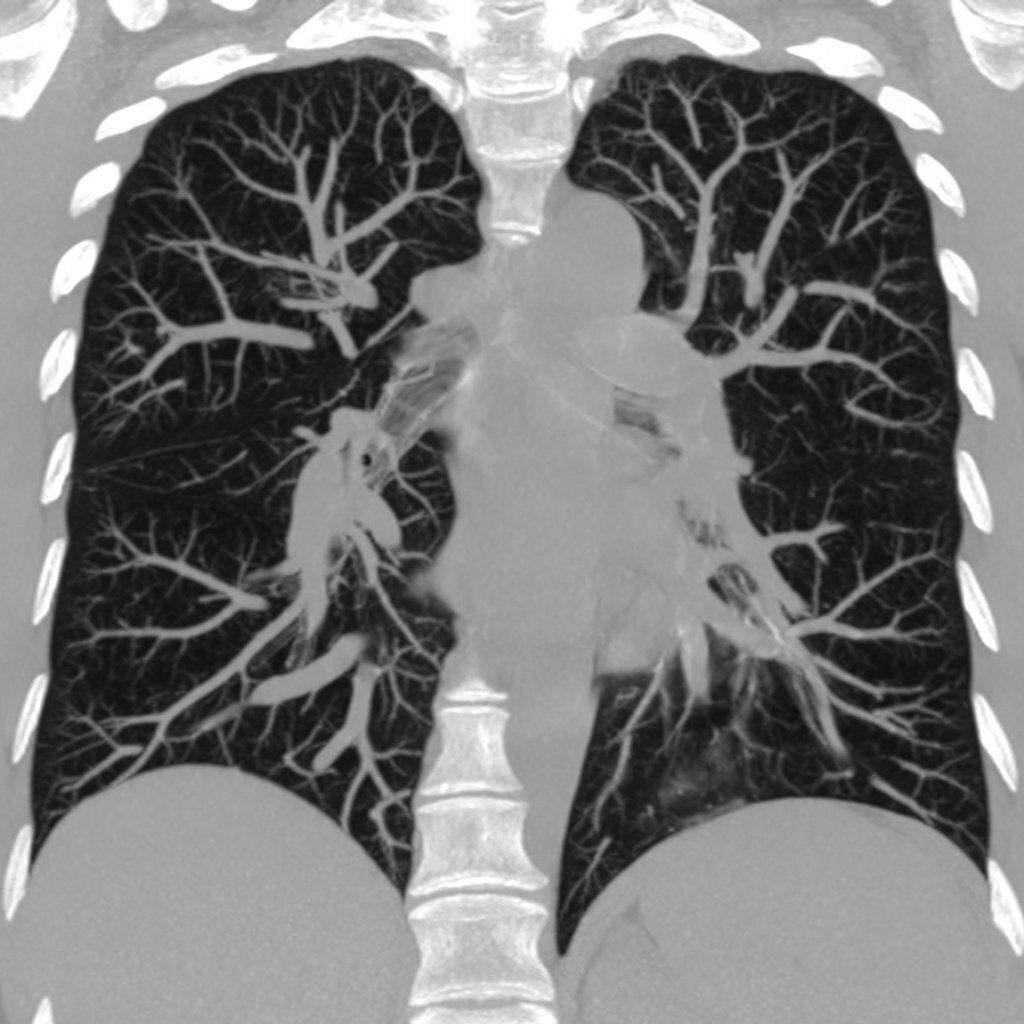

2. Чем КТ отличается от рентгенографии?

КТ это послойное сканирование. При традиционном КТ кольцо сканера делает полный круг, затем стол смещается на заданное расстояние(шаг сканирования), делается следующий "срез". А вот на рентгенограмме изображения органов наслаиваются друг на друга, что мешает их рассмотреть и выявить изменения. Томограмма состоит из нескольких «срезов», что значительно повышает информативность снимков. Чем меньше шаг сканирования, тем лучше видна структура органов, их расположение.

4. Какую задачу решает КТ у пациентов с нетяжелым течением СOVID-19, с которой не сравиться рентген?

Рентген не такой высокочувствительный метод как КТ, и врач не увидит незначительных изменений, а вот наиболее значимые и необходимые для лечения пациентов - легко!